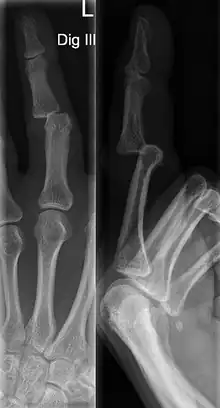

Dislocations can be categorised based on location and type. The finger can be split into three bones and two joints in an alternating order. From the fingertip to the knuckle, these are as follows; distal phalanx, distal inter-phalangeal (DIP) joint, middle phalanx, proximal inter-phalangeal (PIP) joint, and proximal phalanx. DIP dislocations are much less common than PIP dislocations,[2] due to the "stability provided by strong collateral ligaments, palmar plates, and tendinous insertions, as well as the short lever arm of the distal phalanx".[7] Dislocations can be categorised based on the direction that the fingertip moves in relation to the knuckle, be it in the direction of the palm (volar dislocation), or the direction of the back of the hand (dorsal dislocation). Of the two, dorsal dislocations are more common.[3] If reduction has been attempted, an x-ray of the dislocation should appear concentric if successful.[2] However, if there is a fracture present, there will be a misalignment of the joint, which will be evident from the radiograph.[2] Bach suggests a referral to a hand surgeon if a misalignment is present.[2]

Fractures are instances where the bone's structural integrity has been compromised. This is indicated by midshaft pain, as well as visual midshaft angulation or rotation.[3] As with any skeletal injury, an x-ray can be conducted to verify the presence of a fracture.[1] The distal phalanx is especially vulnerable to avulsion fractures, where a fragment of bone is ripped off when the tendon separates from the phalanx.[1] Avulsion fractures are especially common following a first time dislocation.[1] These are especially concerning, as it may indicate a complete tear of the extensor digitorum tendon. If left untreated, this may lead to permanent DIP extensor lag (inability to fully straighten the finger).[8]